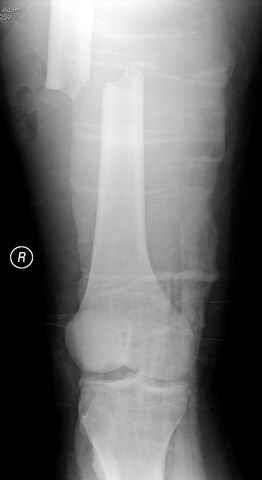

03.14.2005

больному 42, автоавария, политравма, открытая черепномозговая травма, безсознании, открытый перелом бедра, размозжение мягких тканей, дефект кожи на передней поверхности бедра около 13 см2 от ожога, компартмент синдром.

перелом бедра

постоперационные

спасибо за урок, критику принимаю, постараюсь исправится. Уточнения: даты написаны автоматически и надо читать 14-19-24-28 Марта 2005 года, также хирургическая обработка вместе дебрайдмент. (фотографии рентгенограмм скопированы с цифрового ренгенологического архива, извините за качество)